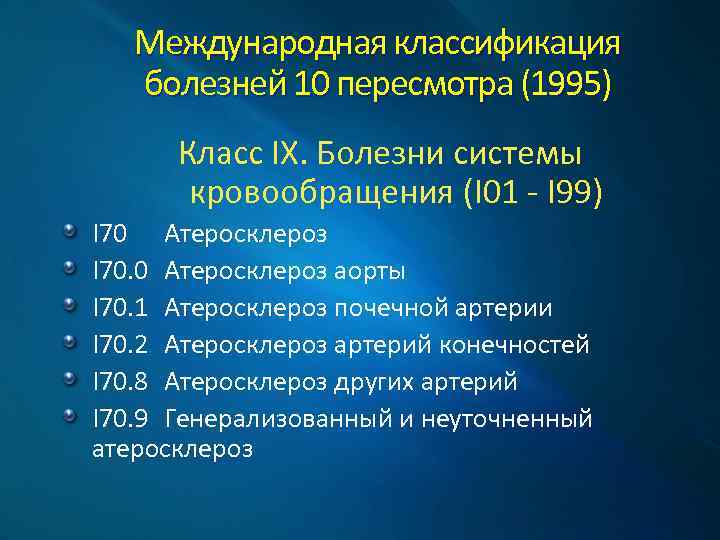

Международная классификация болезней 10 пересмотра (1995) Класс IX. Болезни системы кровообращения (I 01 - I 99) I 70 Атеросклероз I 70. 0 Атеросклероз аорты I 70. 1 Атеросклероз почечной артерии I 70. 2 Атеросклероз артерий конечностей I 70. 8 Атеросклероз других артерий I 70. 9 Генерализованный и неуточненный атеросклероз